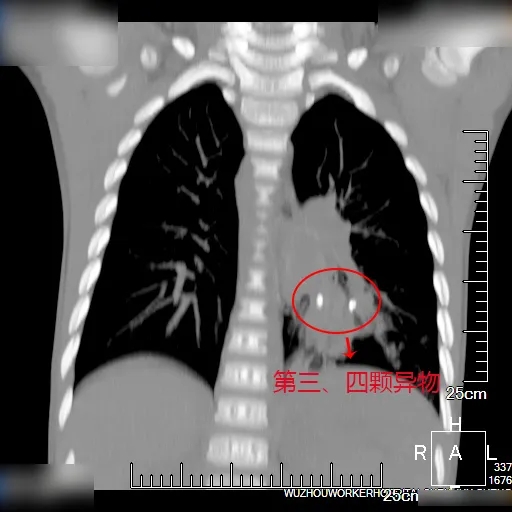

经充分准备,7月19日中午,小安的手术开始。儿科、耳鼻喉科、胸心外科等多学科联合会诊(MDT)团队在手术室就位待命。麻醉科为小安实行喉罩全身麻醉后,儿科支气管镜团队在镜下发现其左主支气管内巨大异物,遂予异物钳钳取,但异物过大难以通过声门下气管,经多次钳取后终取出。再次进镜发现左下肺有大量脓痰,予灌洗清理脓痰。清理完毕,发现其左肺下叶有1颗米粒大小砂石样异物,再次予钳取。经过多次清洗,先后发现3颗米粒大小砂石样异物,均予负压吸出。

术毕,小安转回儿科观察室进行后续治疗。当天17时,小安已能拔除喉罩转为普通吸氧,20时小安可以进食流质食物。7月23日,儿科支气管镜团队为小安复查支气管镜,经肺泡灌洗再次发现小安肺部左下叶与右上叶有异物,予负压吸出。目前,小安正在我院接受后续治疗,并定期复查胸部CT。

(左图为堵塞支气管的大直径异物,右图为左肺下叶小异物)